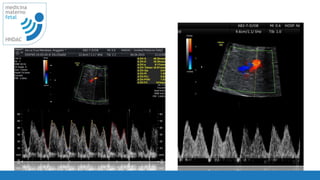

Optimizacion

requerimientos

ausencia de movimientos fetales y maternos

suspender respiración materna

angulo de insonacion menor 20

optimizar escala de grises

optimizar el volumen de muestra de acuerdo al

tamaño del vaso

corroborar la velocidad del filtro menor a 60Hz

visualizacion de ondas 4 - 6 ondas

PRF de acuerdo al vaso que se estudia